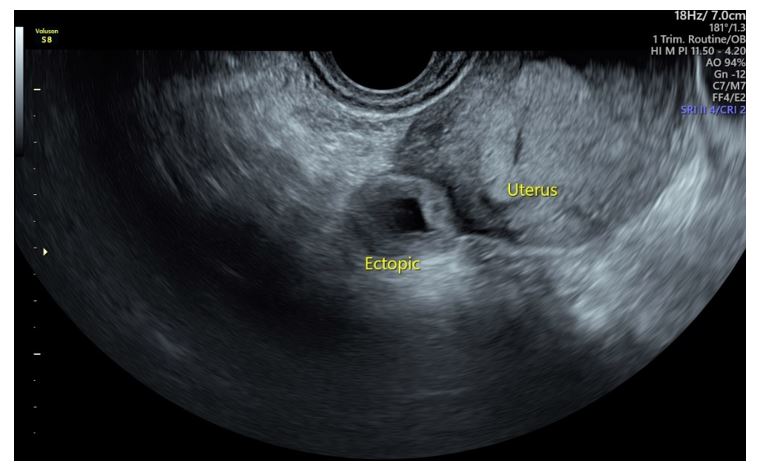

The TVUS (Figure 1) revealed a right sided ectopic pregnancy.